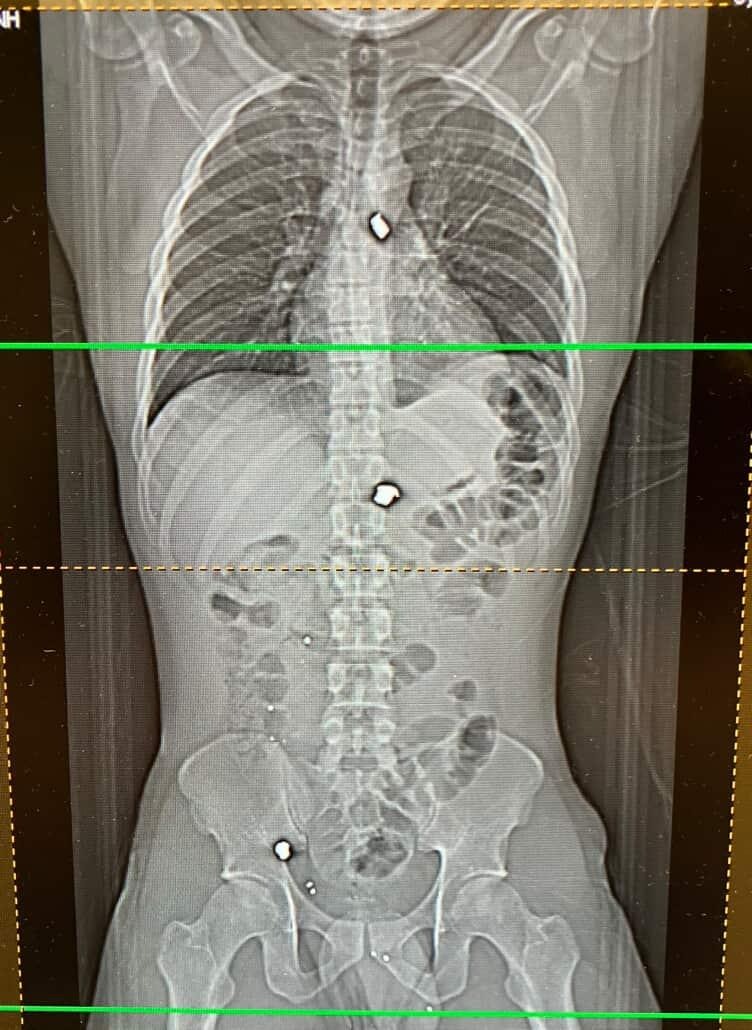

My son Ryan Bradley 29 father of son age 4. was the victim of Walmart shooting in Covington Georgia. Right now he is in ICU pulling through. This has truly been devastating time for our family. We are extremely grateful for his survival and the support from others. Anything will help for transportation back in forth to doctor's appointments and his monthly expenses. Thank you all for your support!